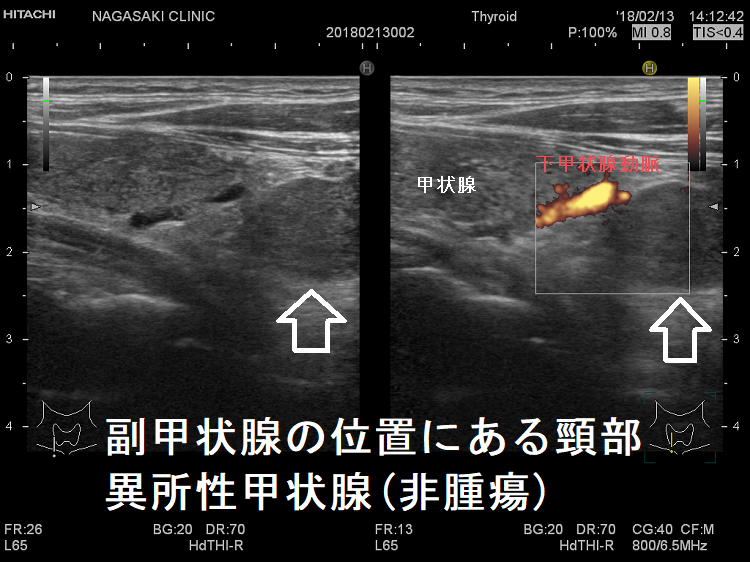

副甲状腺の位置にある異所性甲状腺

頚部異所性甲状腺:下極の副甲状腺と同じ位置にある異所性甲状腺。エコーが減衰してやや黒く(低エコーに)見えますが、橋本病の甲状腺本体と同様、内部粗雑な組織です。

副甲状腺の位置にある頸部異所性甲状腺(非腫瘍)

頚部異所性甲状腺:下極の副甲状腺と同じ位置にある異所性甲状腺(非腫瘍)。橋本病の甲状腺本体と同様、内部粗雑な組織です。

副甲状腺の位置にある頸部異所性甲状腺(非腫瘍)ドプラーモード

副甲状腺の位置にある頸部異所性甲状腺(非腫瘍)ドプラーモード;下甲状腺動脈より下で、かつ甲状腺と連続していないため、分葉でなく異所性甲状腺。